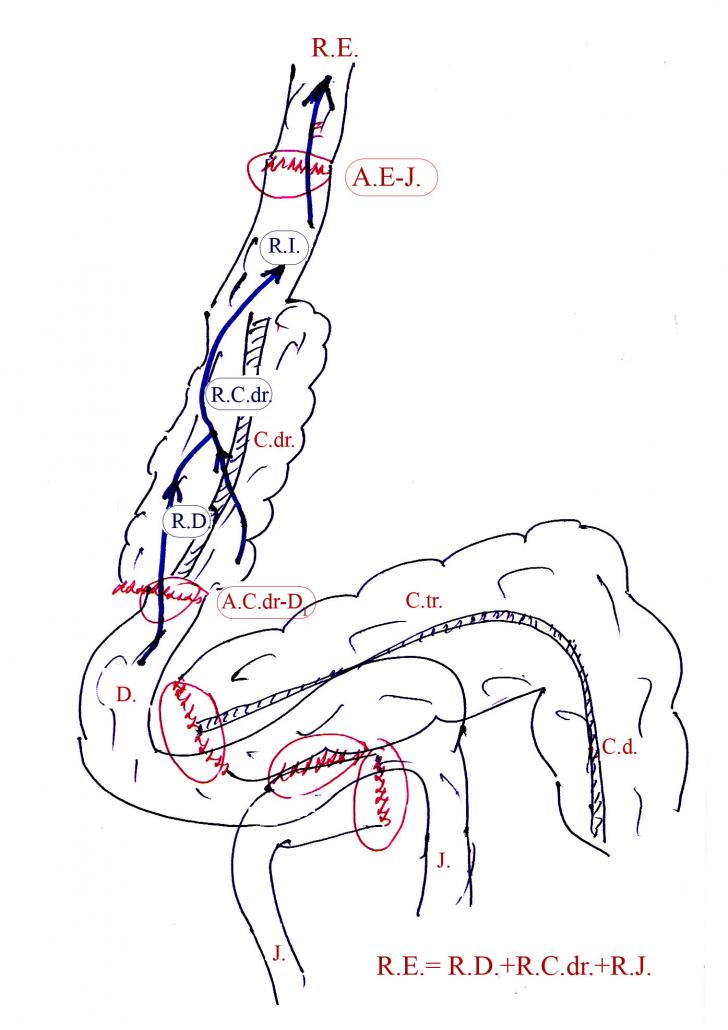

Citeste mai mult « 3569 cuvinte, 8 pag. » OPERATII ANTIREFLUX.

Fig.

84.

Diag.

Reflux esofagian alcalin dupa gastro-ileo-colondrept plastie

dupa

Gastrectomie

totala pentru gastrita Ménetrier.

Sagetile

arataCiteste mai mult « 1236 cuvinte, 3 pag. » GENETICA